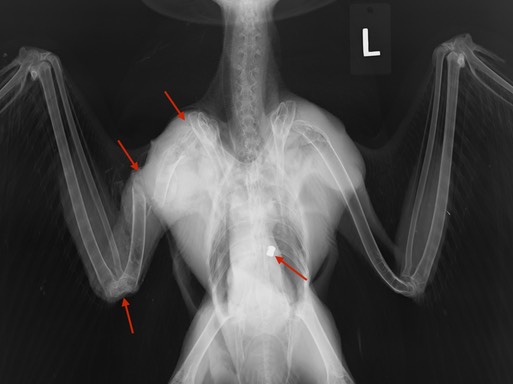

Two Great Horned Owls and a Sharp-shinned Hawk also had injuries too extensive to repair. The Great Horned Owl below had a humerus fracture that was totally unrelated to the air rifle pellet near her backbone. She was shot at a minimum of several months ago. The wound had completely healed. She was in excellent condition until a collision of some type (perhaps with a car or power line) resulted in her broken wing.